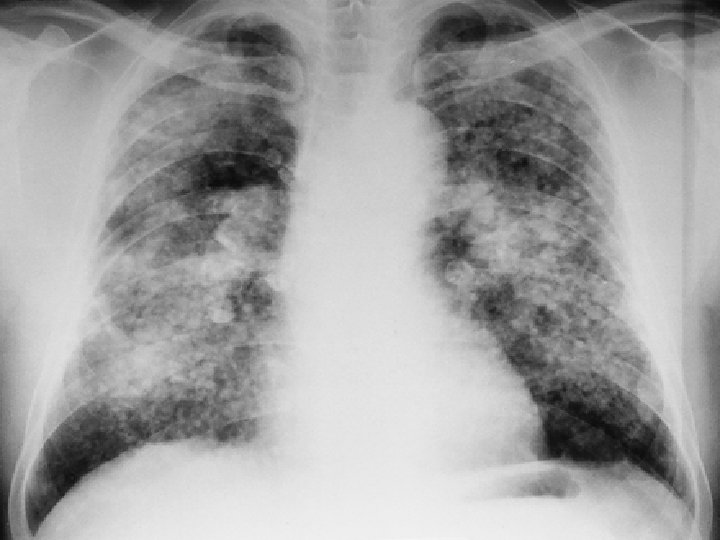

TB l 51 yaşında, işçi l Erkek l Doğum yeri: Zonguldak l

l ŞİKAYETİ Öksürük Koyu renkli balgam Efor dispnesi

l FİZİK MUAYENE: siyanoze, dispneik çomak parmak mevcut DSS: 26 (torako abdominal) OSKÜLTASYONDA bilateral inspiratuvar raller TA: 130/80 Nb: 86/dk

FVC % 55 l FEV 1/FVC %82 l Pa 02 50 mm. Hg l Pa CO 2 38 mm. Hg l

TANI ? ? ?